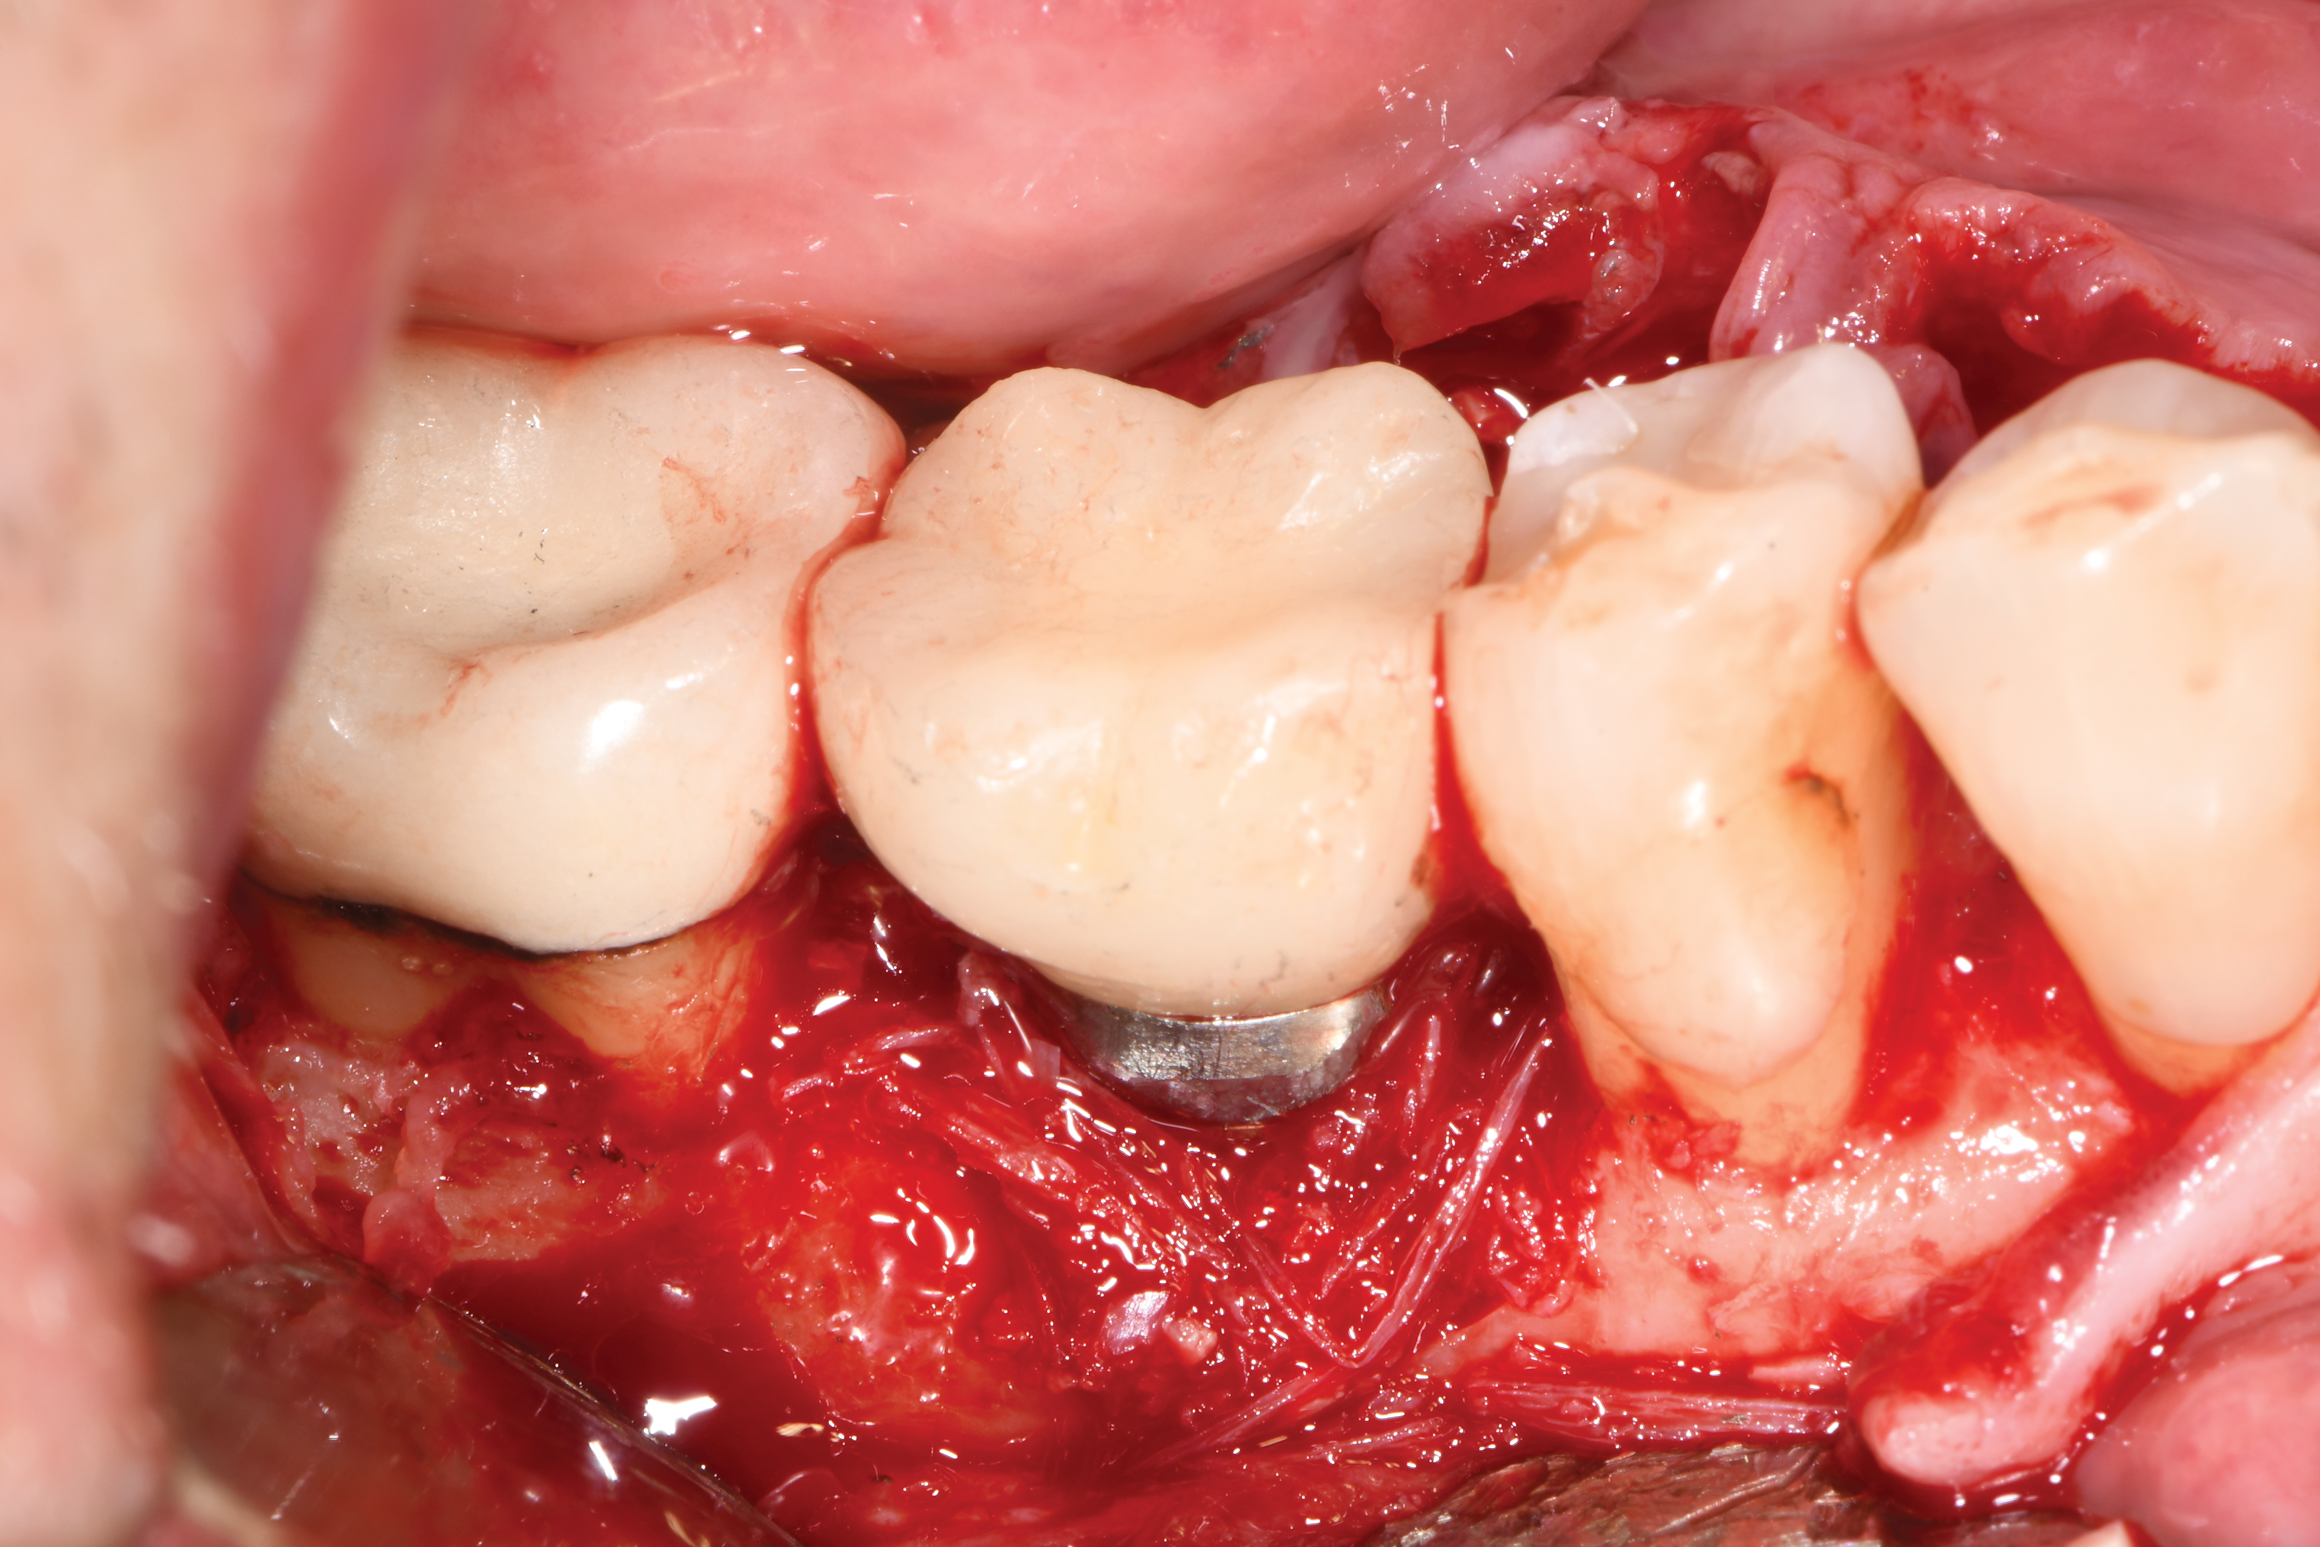

Fig 12. The lesion was visualized upon flap reflection. A three- to two-wall lesion on the mesial wrapped to the lingual, while the distal had a two-wall lesion that also extended to the lingual as a moat.

Figure 12

After local anesthesia was administered, full-thickness flaps were elevated from the buccal and lingual aspects of tooth No. 27 to the distobuccal and lingual aspects of tooth No. 31. Removal of granulomatous tissue from the implant site allowed visualization of a combination lesion with two walls at the distal and two to three walls at the mesial with a circumferential configuration on the lingual (Figure 12). The surface was initially treated with a 50% solution of citric acid for 30 seconds, which was burnished on with cotton pellets followed by thorough rinsing with sterile saline. This was followed by implantoplasty using 12-fluted followed by 30-fluted surgical-length finishing burs that provided access to the base of the defect. Because the crown was cemented, which obviated access, a matte-like surface could not be achieved; thus, the goal was to reduce the threads and remove the outer affected surface to expose fresh titanium (Figure 13). At this stage, the implant was wiped again with citric acid and rinsed with sterile saline.